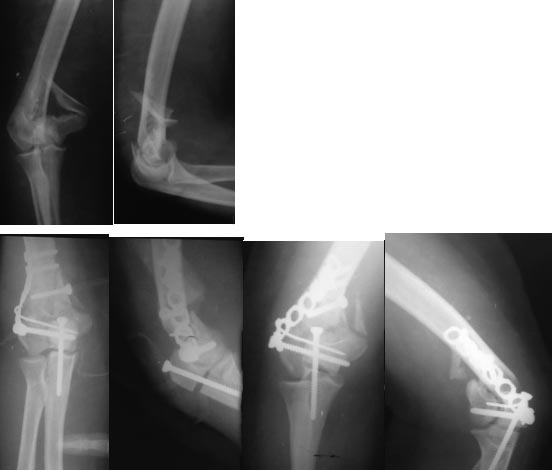

Пациентка Е., 24 года, травма 3.05.13 в следствии

падения на левую руку. Закрытый многооскольчатый перелом дистального

отдела левой плечевой кости со смещением, закрытый перелом левой лучевой

кости в типичном месте без смещения. Операция 7.05.13 (остеотомия

локтевого отростка, открытая репозиция, МОС). В

послеоперационном периоде перевязки, косыночная повязка. Присутствует

неврит лучевого нерва, выражен отек мягких тканей. Через 5 суток с

момента операции, после сна пациентка пожаловалась на хруст в области

перелома, выполнен контрольный снимок. Подправить закрыто

после снятия швов и одеть гипс шину? Выполнять ресинтез? В какие сроки?

Удалять конструкции и фиксировать в аппарате вн. фиксации?